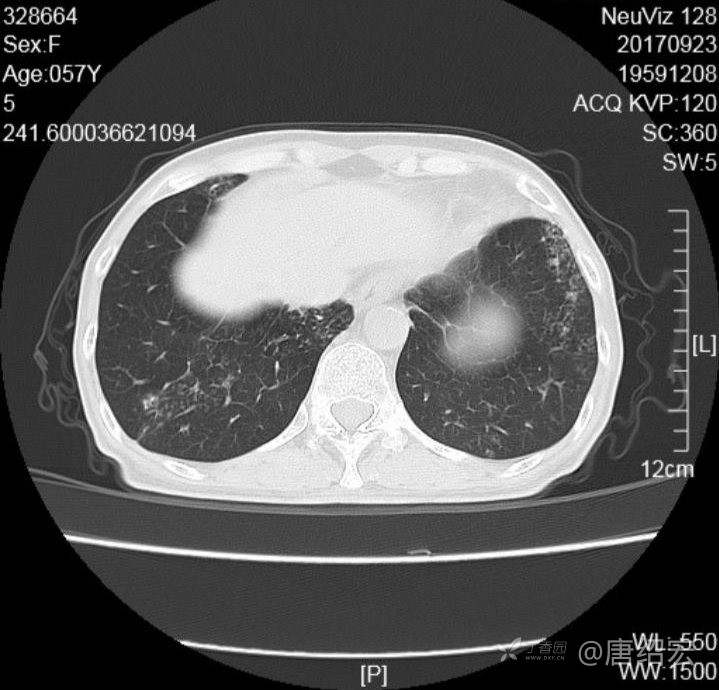

中年女性满肺树芽征还有支气管扩张,考虑什么疾病?

女,57岁,

主诉:发热、咳嗽、咯黄痰,胸闷3天入院。

铜绿假单胞菌性肺炎 (12)

铜绿假单胞菌感染 (20)